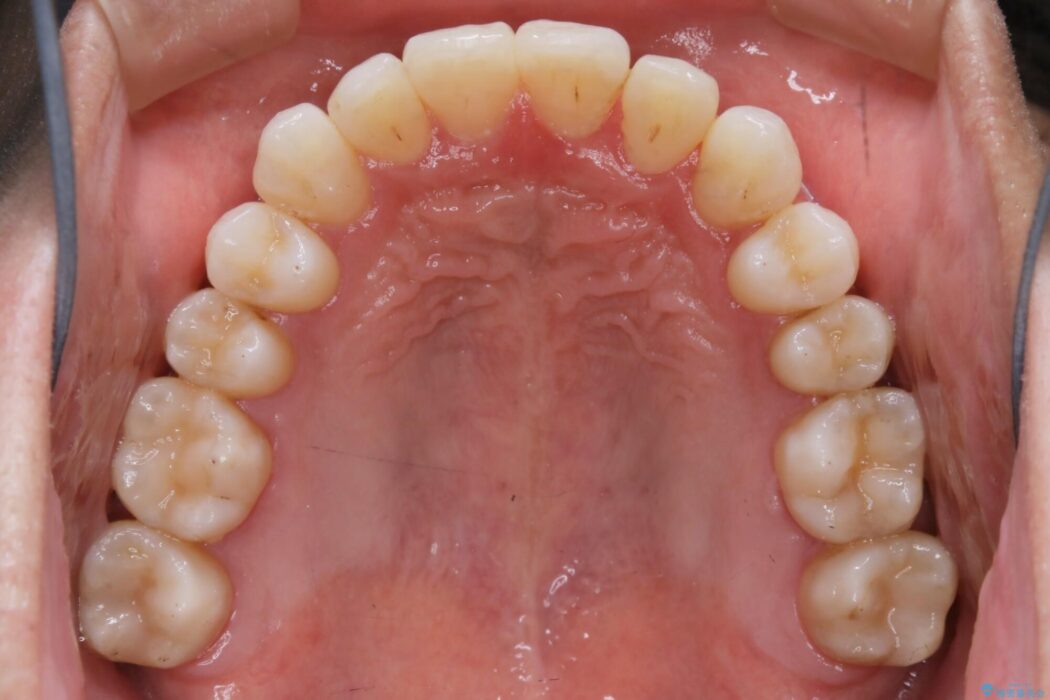

【20代男性】上顎のガタガタな歯列をインビザラインで矯正治療

目立たない矯正装置をご希望されていたため、インビザラインでの治療をご提案しました。

前に出ていた前歯や目立つ八重歯(3番目の歯)もきれいに並び、奥歯の虫歯治療も並行して行ったため、機能面でも見た目的にも良くなり満足していただきました。

非抜歯での矯正治療ではスペースの確保が必要となります。

本症例では上記3つの方法を複合的に組み合わせた治療を行いました。